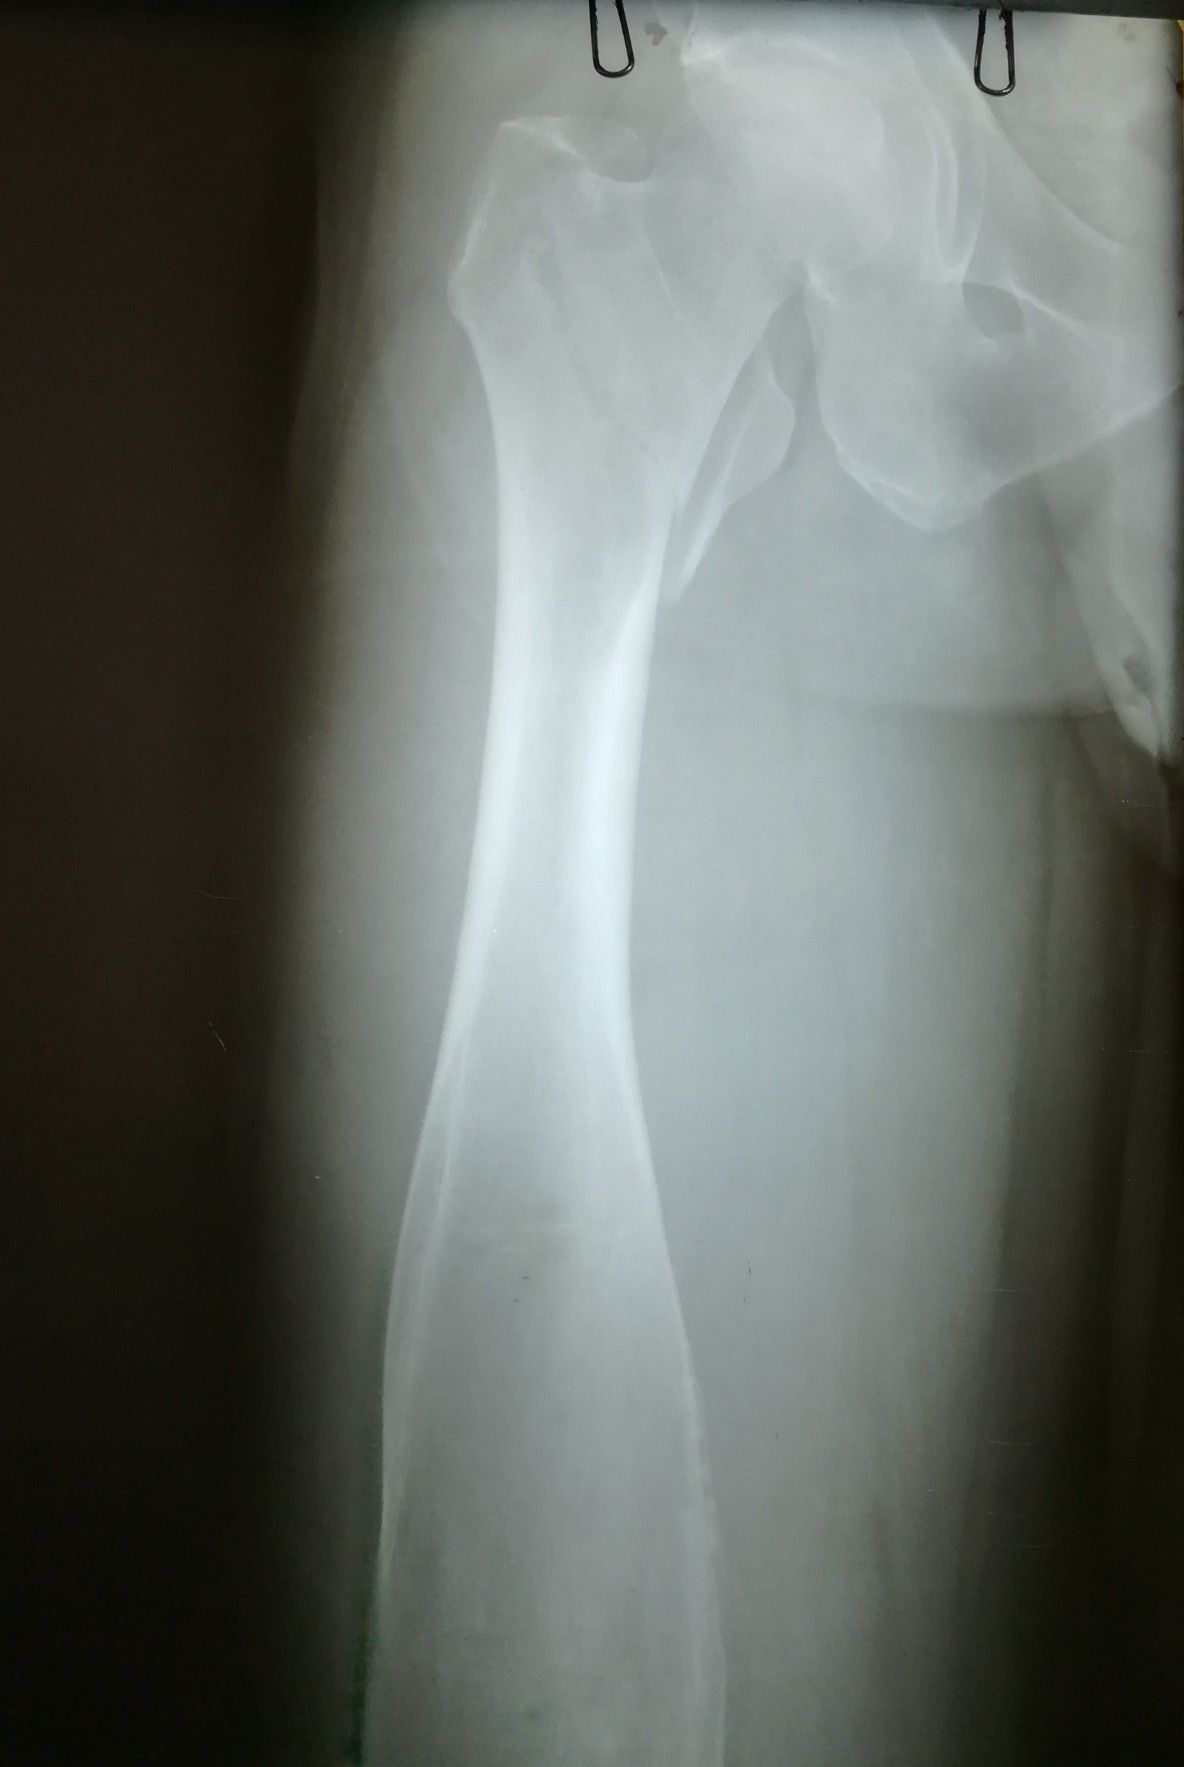

What is the reason for enlargement of the femur shaft? Is it a tumor?

46yr male patient presented with right side pertrochanteric fracture after trauma. Also he has a history of left side femur head fracture 2 years back due to an accident....